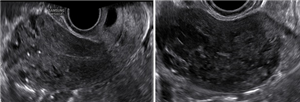

Tăng sinh mạch máu cơ tử cung - thông nối động tĩnh mạch mắc phải

Xem thêm